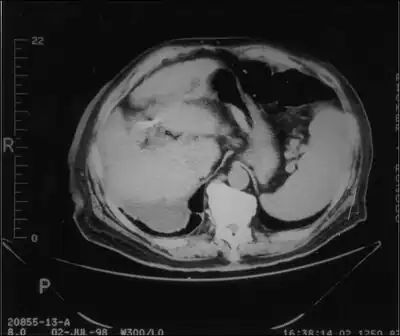

Streptococcus bovis (S. bovis) is a species of Gram-positive bacteria that in humans is associated with urinary tract infections, endocarditis, sepsis, [5] and colorectal cancer.[6] S. gallolyticus is commonly found in the alimentary tract of cattle, sheep, and other ruminants,[7] and may cause ruminal acidosis or feedlot bloat.[8][9] It is also associated with spontaneous bacterial peritonitis, a frequent complication occurring in patients affected by cirrhosis.[10] Equivalence with Streptococcus equinus has been contested.[4]